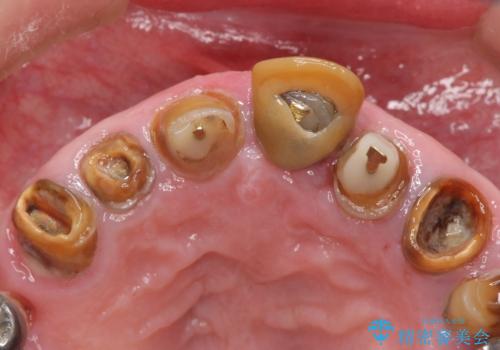

前歯4本のうち3本の被せ物が脱離し、残りの1本の被せ物は劣化し変色していました。

古い被せ物や土台・虫歯をしっかり除去したのち、セラミック治療を行いました。

患者様のご希望により、根尖病変の明らかな左上2のみ根管治療を行いました。

- ¥610,000 (根管治療×1本、土台×4本、仮歯×4本、クラウン×4本)費用は治療当時の料金となります